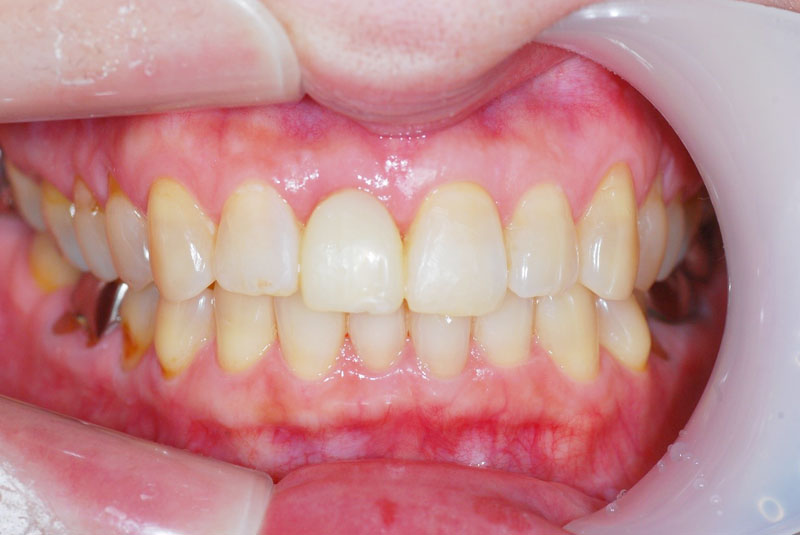

前歯のインプラント

-

術前

術後

- 患者

- 30代女性

- 主訴

- 他院で治療中の歯が折れて無くなった。

前医で前歯の治療を数か月していたが抜歯を勧められた。悩んでいたところ歯が折れてしまった。

- 治療経過

- 両側の歯を削りたくないのでインプラント治療を希望された患者さんです。前歯部インプラントの難易度はずばり審美性です。前歯なのでできる限り隣の歯と合わせる必要があります。特に1本欠損で両側が天然歯というのは難易度の高い症例です。この患者さんは決断が早く、歯槽骨まで感染が及んでいなかったため抜歯と同時のインプラント埋入を行うことで骨移植等を行うことなく治療可能でした。前歯は場合によっては審美性を確保するために歯肉移植が必要なことも多く、当院では歯肉移植を行うかどうかは患者さんと相談させていただいております。

- 治療費

- インプラント検査 3.3万円

前歯部インプラント手術 24.2万円

抜歯即時埋入加算 3.3万円

インプラント仮歯 1.5万円

アバットメント 7.7万円

ジルコニアレイヤリングクラウン 13.2万円

計 53.2万円

- 治療回数・期間

- 8回 9か月

- リスク

- 手術後の腫脹、出血、疼痛

術後感染

インプラント脱落

インプラント周囲炎

上部構造破折

歯肉退縮による審美障害

自由診療で保険が効かない